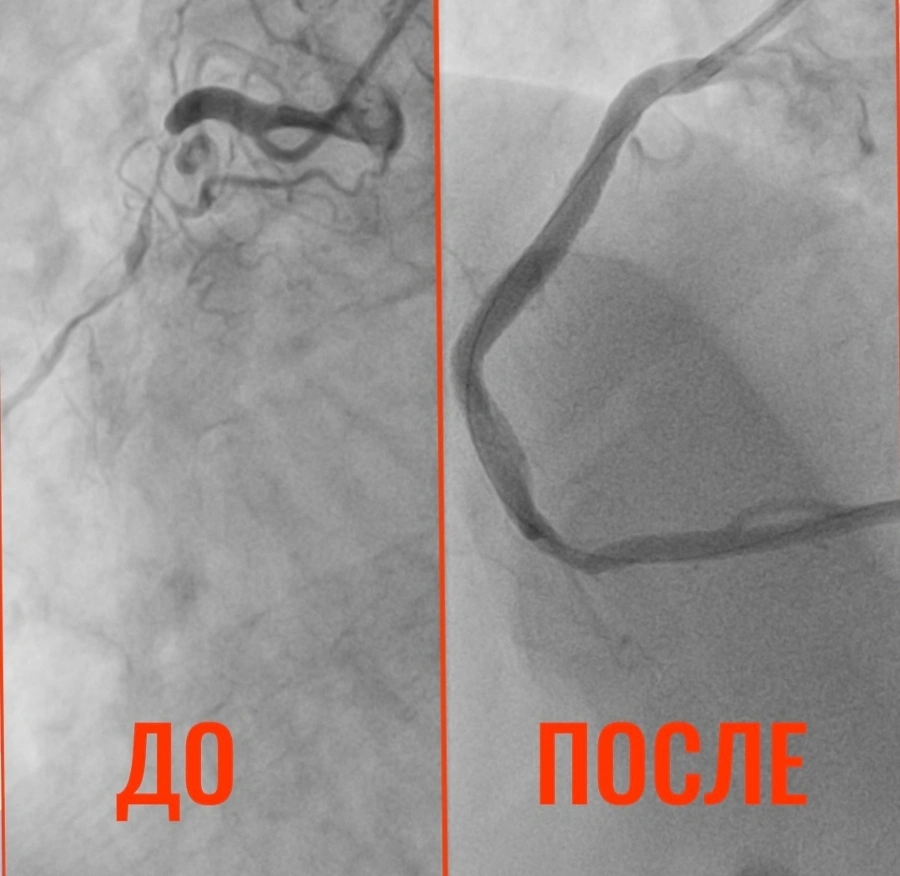

Как сообщает Балаковская городская клиническая больница (БГКБ), в приемное отделение поступил 32-летний житель города Пугачева, который страдает гипертонической болезнью с 15 лет. Во время планового лечения в терапии БГКБ он пожаловался на боли в сердце. При выполнении коронарографии врачи были шокированы: сужение просвета коронарной артерии достигло 90%! Кровь почти перестала поступать к сердцу. Состояние сосудов 32-летнего мужчины специалисты сравнили с изменениями, характерными для глубокой старости — были поражены все три коронарных артерии. Чтобы предотвратить инфаркт, врачи приняли решение об экстренной операции.

«3 марта пациенту провели стентирование. Установлено три стента, кровоток восстановлен полностью. Сейчас состояние пациента стабильно, впереди — реабилитация и консультации с областными коллегами по телемедицине», - рассказали в БГКБ.